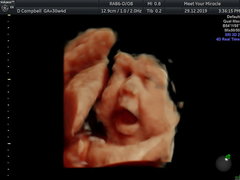

Here's my little fatty. Look at his cheeks and lips 😂😍

March Babies #5

@whiskersonkittenss he's adorable!!! How far gone are you? X

@whiskersonkittenss Omg those are amazing, how clear are those images?! He's so cute! X

@whiskersonkittenss those scan photos are so cute! I had a 3D scan a few weeks ago and I wish I waited a bit longer until baby got a bit chubbier😍